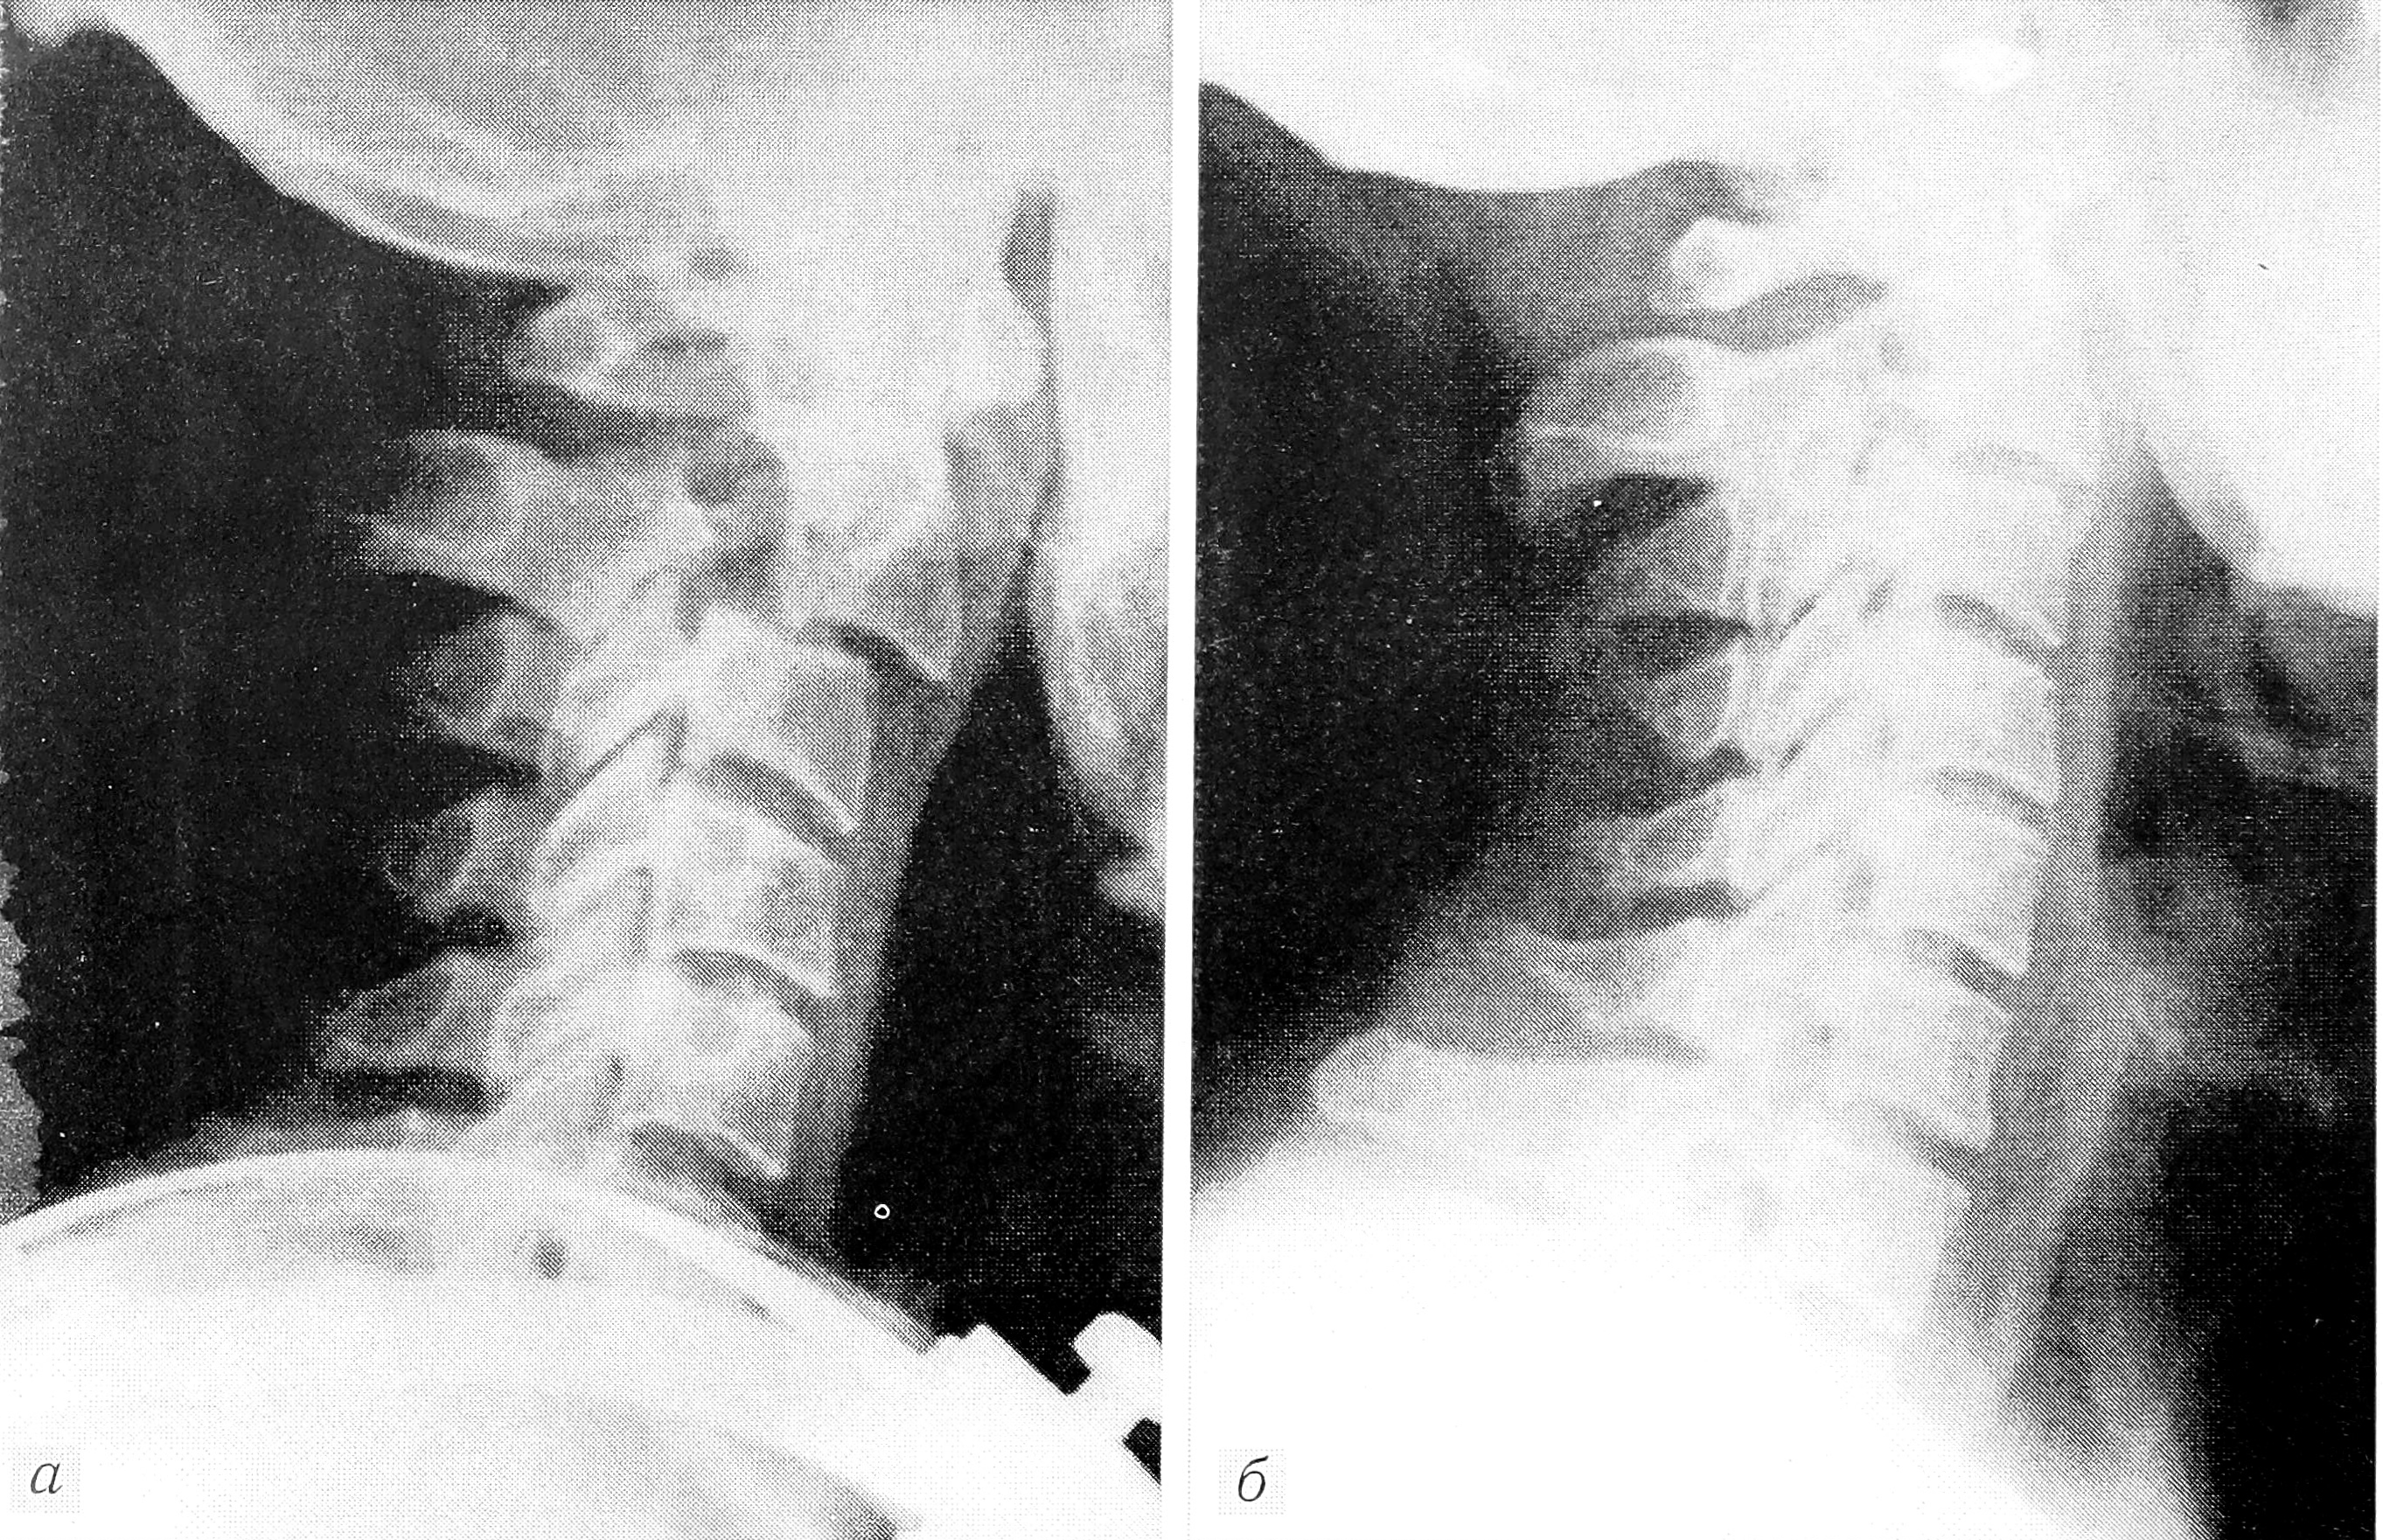

Рис. 2. Функциональные рентгенограммы больной З. через 2 года после травмы.